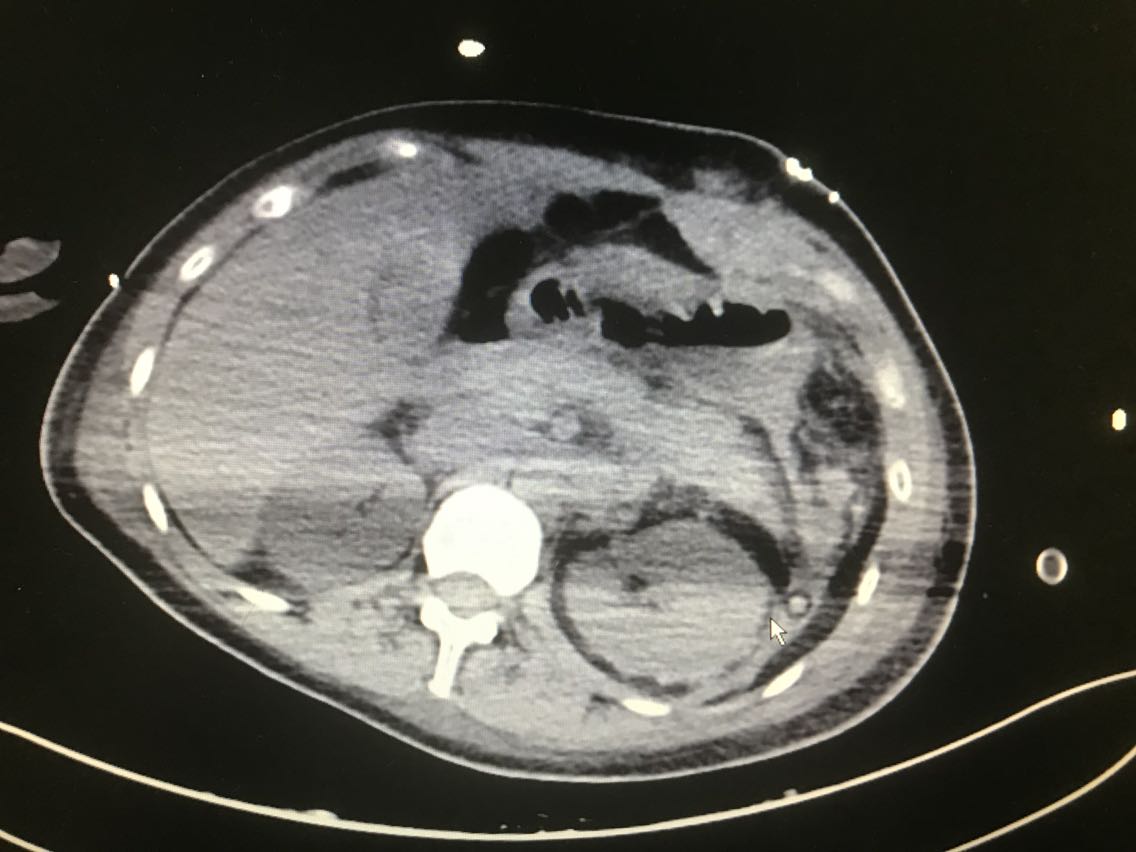

患者女性,31岁。 主诉:体检彩超发现左上腹异常回声10天 现病史:入院前10天,患者当地医院体检时彩超发现左上腹异常不均质稍低回声区,患者无胸闷胸痛、头晕黑朦、腹痛、乏力等不适,血压未见明显升高,近期体重未明显增加,二便正常,未予特殊处理。6天前患者于当地医院行增强CT检查示:左肾上极与胰脾之间肿瘤,疑为左侧肾上腺嗜铬细胞瘤,患者仍无胸闷胸痛、头晕黑朦、腹痛、乏力等不适。患者于我院就诊,诊断为左侧肾上腺肿瘤。患者目前为求进一步诊治,今日入住我科。 既往史无特殊。

查体:无特殊。 辅助检查: 腹部彩超示:左上腹见大小约10.8*7.0*6.9cm异常不均质稍低回声区,其内见大小约0.5*0.5cm强回声点。 全腹增强CT示:左肾上极与胰脾之间肿瘤:左侧肾上腺嗜铬细胞瘤?。

诊断:左侧肾上腺肿瘤。 治疗:腹腔镜左肾上腺肿瘤切除术+肠粘连松解术+左肾周粘连松解术 术中见:左肾上腺肿瘤约8x8x7cm肿瘤,肿瘤滋养血管增生紊乱,左肾上腺肿瘤与左肾上极及周围组织粘连,左肾周粘连。